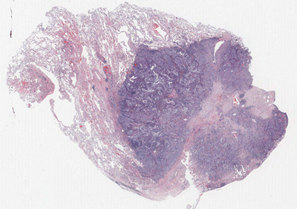

Lung cancer is one of the most deadly cancers (Siegel, Miller and Jemal, 2020). One of the most common types of lung cancer is adenocarcinoma which accounts for about 40% of all lung cancers (Zappa and Mousa, 2016) and has various morphological features (Matsuda and Machii, 2015). We use 230 pathology images of 133 lung adenocarcinoma patients in the National Lung Screening Trial (NLST) data. All images are obtained under 40X magnification, and the median size of images is 24,24419,261 pixels. The image patches of size 300300 pixels (7575 microns) are segmented into three classes of the tumor, normal, and empty regions using a deep convolutional neural network (CNN) (Wang et al., 2018). For example, for a given NLST pathology image of size 30,00030,000, the CNN model generates the segmented image of size 100100. We implement an additional pre-processing step to remove noise: a single pixel is considered to be noise when its class is different from the surrounding eight singular-class pixels, and the noise pixels are reclassified to the class of the surrounding pixels. The denoised three-class images are transformed using the SEDT-3. Figure 5 presents the pathology image, the segmented three-class image of Wang et al. (2018), and the SEDT-3 image.

A sequence of cubical complices is constructed using the SEDT-3 values as filtration, and persistent homology is computed using GUDHI (Dlotko, 2015). We replace the dimension-zero result with infinite death value with and exclude the dimension-one result with infinite death value to remove features related to empty regions. The median number of the computed features per image slice is 694 for dimension-zero and 1,768 for dimension-one. The ranges of persistence diagrams are for dimension-zero and for dimension-one. The smoothing parameters and are used for the persistence surface functions.